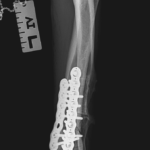

大型犬の橈骨遠位変形矯正をPaley’s ruleを元に、Center Of Rotation Angulation(変形中心角)を決定し、vPOPでシミュレーションを行い骨切り矯正術を行った。機能軸もしくは解剖軸を骨軸上に配列できなければ2次的な変形が生じてしまうリスクがある。橈骨遠位のCORAを中心にラウンドオステオトミーを実施3.5 Locking PlateでOrthogonal法で整復固定を行う。このテクニックでは骨切除を行わないので脚短縮が生じないというメリットがあります。